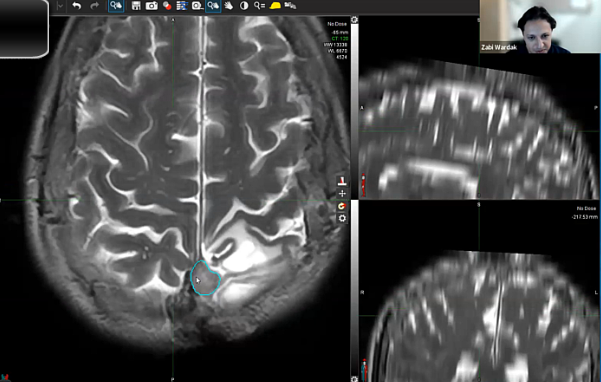

08/22/2023 - Dr. Zabi Wardak - Radiation Oncology - SBRT

SRS, dose, recurrent GBM,